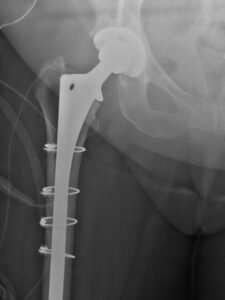

Revision hip surgery often involves osteotomy to extract the previous component and longer stems with distal fixation or fixation along the entire length of the stem.

As with the normal total hip replacement procedure, this may involve using cement to fix the components in the hip socket and thigh bone. Revision implants usually are longer than those used in primary THR and may involve more constraint at the bearing surface.